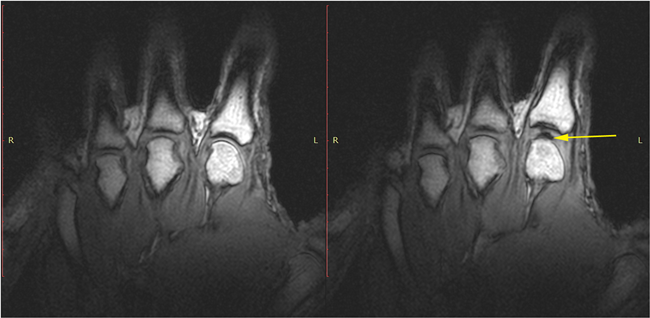

นักวิจัยจาก University of Alberta ได้ตีพิมพ์เรื่องเสียงที่ดังจากการหักและดึงนิ้ว โดยทดลองจากเครื่องเอกซเรย์คลื่นแม่เหล็กไฟฟ้า (MRI) พวกเขากล่าวว่าเสียงที่ได้ยินเป็นเสียงที่มาจาก “น้ำไขข้อ” และในส่วนของนักวิจัยอีกหนึ่งทีม จาก University of California ก็ได้ค้นหาคำตอบเรื่องนี้ด้วยเครื่องอัลตร้าซาวด์กับผู้คนที่ชอบดึงนิ้วเป็นประจำ และกล่าวว่าเขาเห็นแสงสีขาววูบวาบเหมือนจุดพลุในกระดูก